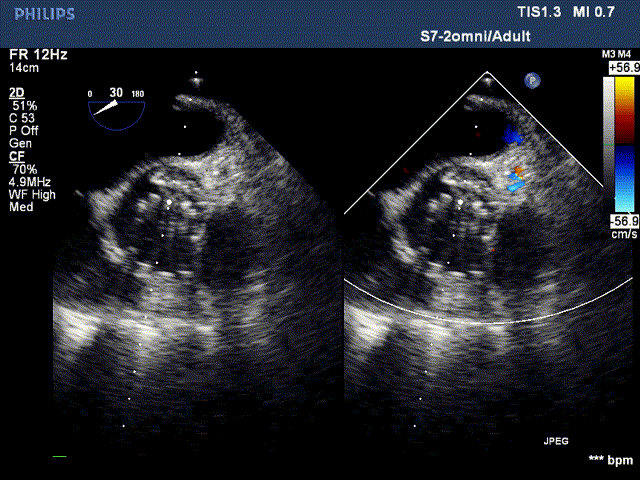

术后超声:

术后超声提示:无瓣周漏,血流动力学明显改善,二尖瓣重度反流改善为轻度反流。